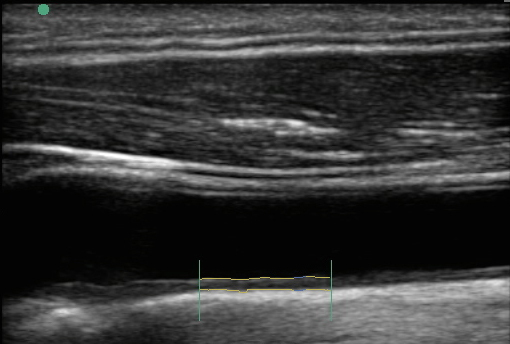

頸動脈 IMT の測定画像

IMT - Intima-media Thickness